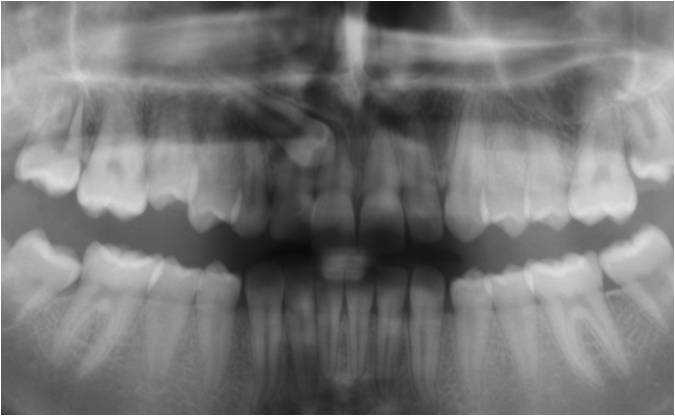

- Panorama viser, om alle tænder er anlagt, og om tandrødder og kæbeled ser normale ud.

- Profilrøntgen giver et billede af, hvordan kæberne er placeret i forhold til hinanden og i forhold til resten af kraniet. Derudover giver det et indtryk af, hvordan væksten vil udfolde sig.

- I nogle tilfælde tages der også et røntgenbillede af hånden, for at se hvor langt dit barn er i sin vækst.

- Der tages røntgenbillede af fortænderne i overkæben som et referencebillede, da disse af og til bliver skadet lidt af en bøjlebehandling. Cirka et halvt år inde i behandlingen bliver der taget ét billede igen som kontrol.

- Alt materiale studeres af en specialtandlæge, der udarbejder en behandlingsplan.